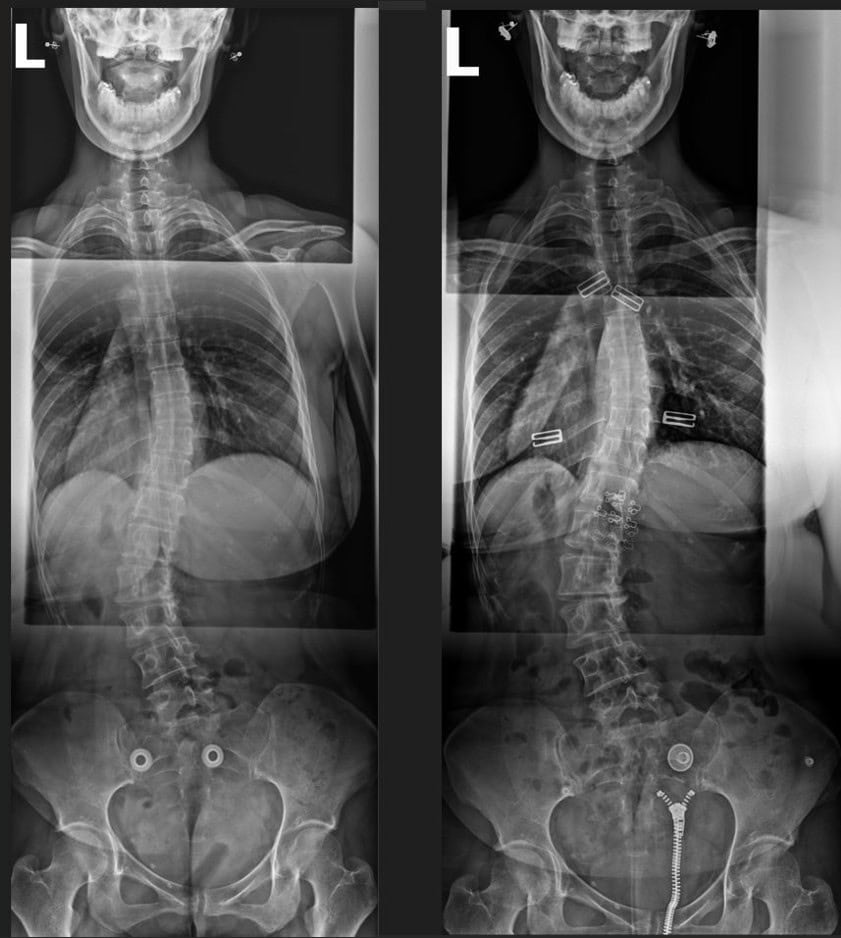

Jillian came to us seeking help for persistent lower-back pain and ongoing digestive issues. These challenges began after she was involved in a motor vehicle accident that resulted in hospitalization and surgery.

Pre & Post Scan